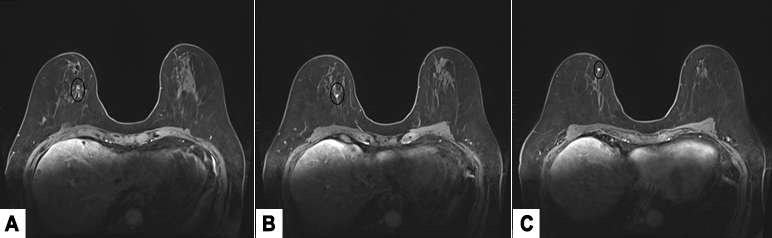

Case: Invasive Lobular Carcinoma Figure 6

A. MRI revealed a linear segmental non-mass enhancement of the upper inner quadrant with fast persistent enhancement kinetics. B, C. There are two additional enhancing foci in the upper inner quadrant demonstrating multifocal disease.